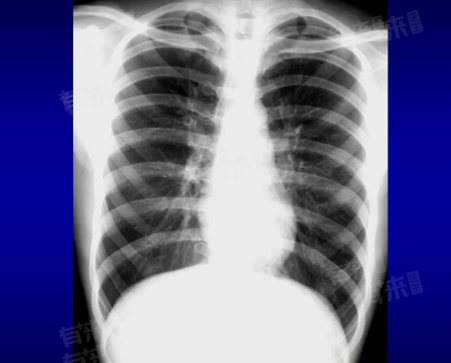

肺部CT片子的解读需要综合考虑多个方面,包括图像质量、肺部结构、病变特征以及临床信息等,通过仔细观察和分析,可以更好地了解肺部的健康状况,为疾病的诊断和治疗提供重要依据。

- 肺部CT图像是胸部CT吸气扫描的横断面示意图,其中胸膜、心脏、骨骼等灰度较高;肺实质和气管腔因充满气体灰度较低,由稍亮的管壁隔开。肺气管、血管在横断面中呈椭圆形,随着气管不断分裂,管腔变窄,管壁变薄,二者与周围实质边界逐渐模糊,肺血管也随分裂在肺边缘处灰度降低。

- 识别肺部结构:识别出肺叶、肺段、支气管、血管等肺部基本结构,注意观察肺门、纵隔等区域有无异常。